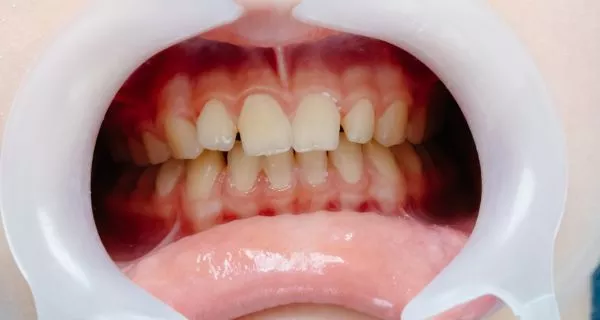

Therefore, gum diseases come, bad breath (Halitosis), and depending on how advanced this infection is, it is possible to observe red, bleeding and inflamed gums, which are initial symptoms of gingivitis and one of the classifications associated with gingivitis is trench mouth, which we will explain in the document.

It is an acute infection of the gums, the most severe form of gingivitis and advanced, meaning it can come on quickly and cause serious damage to your gums and teeth.

Within the social context it is known as a trench mouth; however, clinically it has several diagnoses such as: acute necrotizing ulcerative gingivitis (ANUG), Vincent’s disease or Vincent’s stomatitis. It manifests clinically with bleeding gums, inflammation, pain followed by ulceration between the teeth and gum tissues; which makes this condition quite painful, and is associated with initial or pre-existing gingivitis as a result of poor oral hygiene and that was not treated in time.

It is a severe acute form of gum disease, characterized by rapid deterioration of gum tissue and rapid progression of infection. The main symptoms include:

- GumsRed and swollen gums

- that bleed on slightest contact